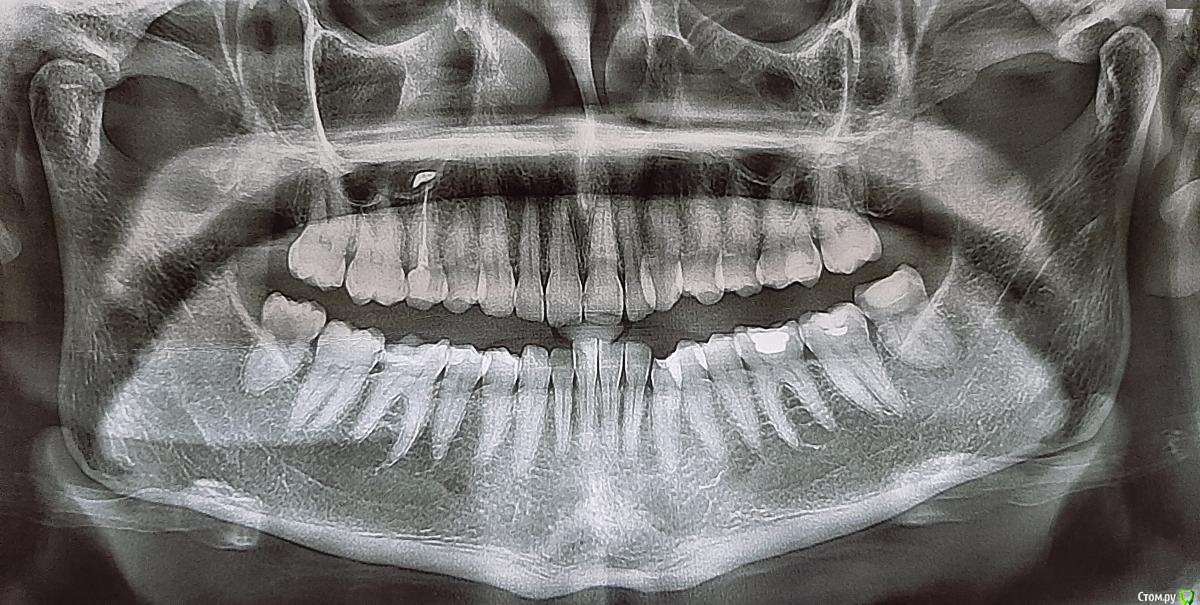

Nad102 Опубликовано 18 июля, 2020 Поделиться Опубликовано 18 июля, 2020 Здравствуйте! Месяц назад откололся верхний зуб мудрости справа. До этого несколько стоматологов говорили, что его нужно будет удалить. Я долго не думая записалась к хирургу. Но через 2 дня заболело горло (у меня хронический тонзиллит) и поднялась температура 37,2. Терапевт назначила антибиотик (супракс) и противовирусные, сказали чтоб зуб пока не удаляла, якобы могут быть осложнения. 6 дней я пила антибиотик, горло успокоилось, но начали болеть висок и ухо справа (вернее это было чувство жжения и распирания, периодически с прострелами). Температура 37,2 так и не снижалась. После двух бессонных ночей, я удалила экстренно 8-ку. После того как вкололи ультракаин чувство жжения и распирания мгновенно сошло. Зуб удалили легко, хирург сказал, что температура не от зуба, воспаление не видет, но зуб кариозный, и действительно его нужно удалить.Через 3 дня после удаления появилась отечность на скуле, появилась небольшая ломота в виске и снова жжение в ухе и щелчки (но щелчки в ухе меня беспокоили давно). После промывания лунки и заложения лекарства боль стихла, но на следующий день все повторилось. Процедуру с промыванием повторили, опять облегчение. В целом стало лучше, но беспокоило ухо. Лор ничего не нашла, патологию уха исключила, назначила немисил, отправила к неврологу. Немисил помогает, дискомфорт и болевые ощущения снимает, но отек держится уже 3 неделю. Он небольшой, еле заметный, но есть, врачи его прощупывают. Невролог поставила заключение: невралгия тройничного нерва 2 и 3 ветвей. Назначение: мовалис, мильгамма, кавинтон, мексидол, амитриптиллин. Стоматолог-терапевт, воспаление во рту не видет, сделали снимок, на 5 верхнем зубе справа выход пломбировочного материала в челюсть. Этот зуб лечили 5 лет назад, никогда он меня не беспокоил. Отек не сходит. Висок побаливает, в ухе дискомфорт. Записана на консультацию к челюстно-лицевому хирургу только через неделю.Помогите разобраться. Вообще у меня ощущение, что это сустав ноет. Прикус у меня не правильный, и в последнее время кажется, что нижняя челюсть как будто сместилась влево. Ссылка на комментарий